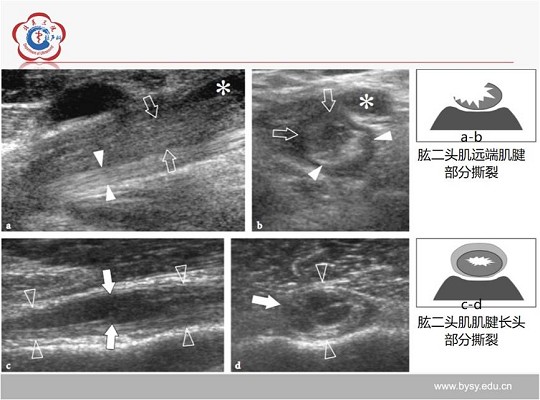

【经典超声书籍解读】肌肉骨胳超声诊断之肌腱病与部分撕裂